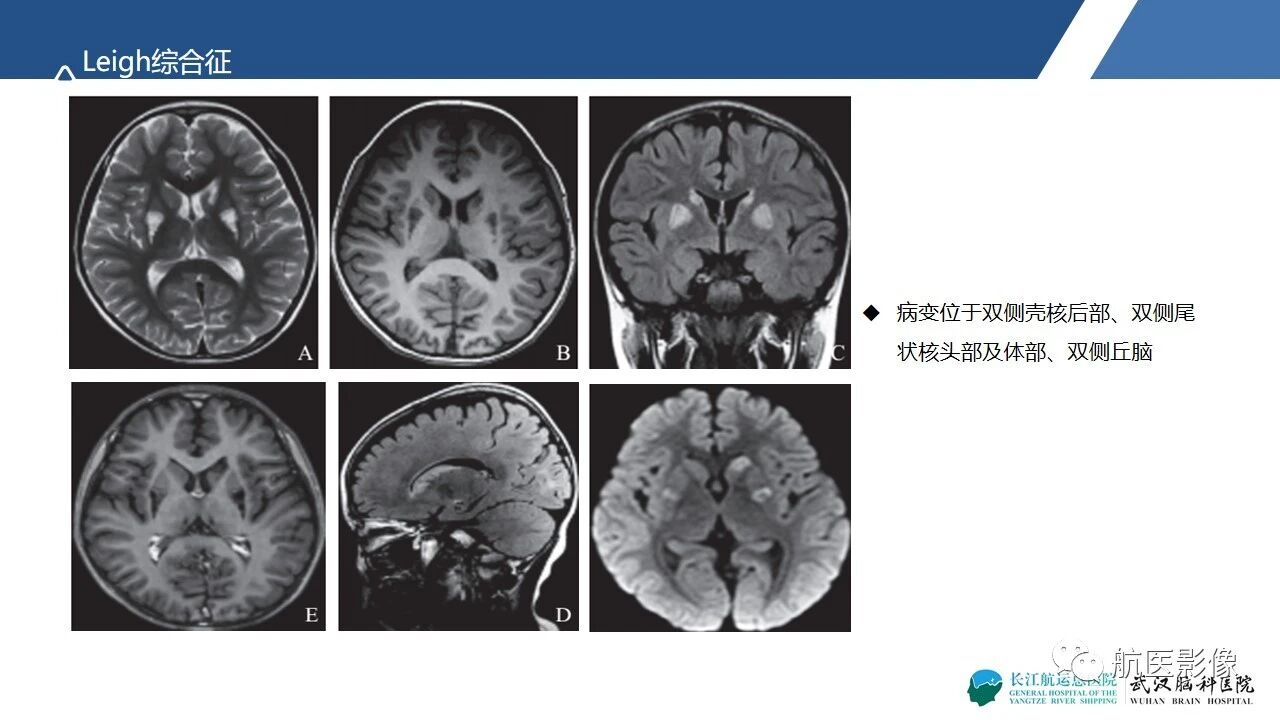

基底节区、丘脑对称性病变影像表现